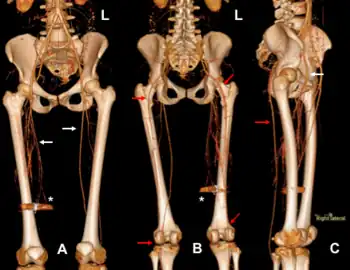

Authors: Sofia M. Ramos, Reinhardt G. Dreyer, Thandi E. Buthelezi

Bilateral persistent sciatic artery (PSA) is a rare vascular anomaly. We report an exceptionally rare case of complete bilateral PSAs, diagnosed on computed tomography angiography (CTA) in a patient who sustained a gunshot wound to the lower limb. Incidental PSAs are unlikely to have clinical significance, however, the unusual anatomy and higher incidence of complications requires accurate reporting of such variants. In this case, the anomaly paradoxically proved beneficial given the proximity of the gunshot wound to the femoral vessels. The embryology, clinical and imaging findings, potential complications, and treatment options regarding PSA are discussed.